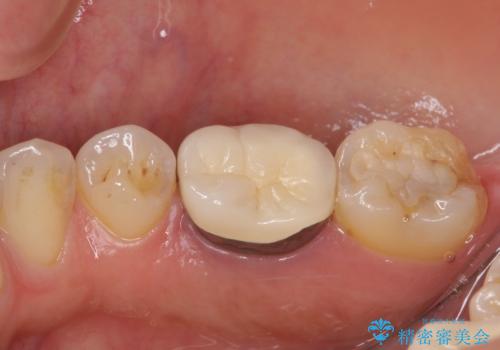

根管治療を行った奥歯は、再発防止や残された歯質を守るため、クラウンによる補綴治療が必要となります。

補綴後6か月経過しレントゲンを撮影したところ、根尖周辺の病変が消失していることが確認できました。